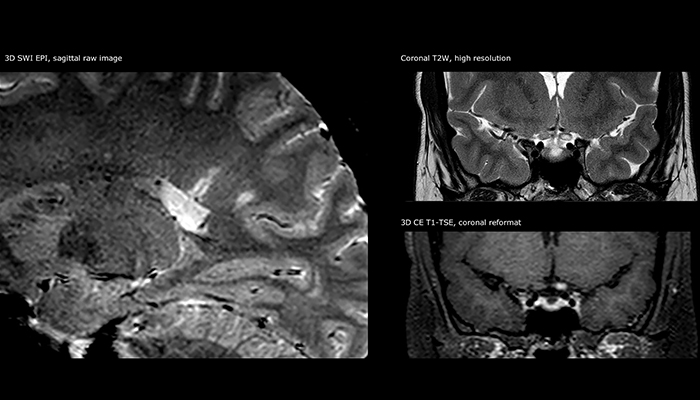

“Ingenia provides great flexibility in the parameters setting. We can tune a sequence the way we want,” says Dr. Savatovsky. “For example, in a stroke exam we use a FLAIR sequence of about two minutes instead of the four-minute FLAIR we use for MS. The diffusion is 30 seconds, the T2*-weighted scan is 30 seconds, the angiography scan time is less than one minute. Ingenia is a great scanner in that situation; even with these fast sequences we can achieve good images with good SNR. When the first sequence tells us that it’s not an ischemic stroke but a hemorrhagic stroke, we may switch to a time-resolved angiography to look for vascular malformations and venous thrombosis.

“Every center is different, but for me the ideal protocol for stroke includes diffusion weighted imaging, FLAIR, and fast susceptibility imaging,” says Dr. Savatovsky. “Our fast susceptibility weighted imaging takes 50 seconds, so it’s as fast as T2*-weighted imaging. It visualizes hemorrhage but also the clots. We also do 3D MR angiography that provides information on cervical and brain vessels. If the patient does not need immediate treatment, or if additional information is needed to decide on treatment, we might also add perfusion imaging and post-contrast T1-weighted imaging.”